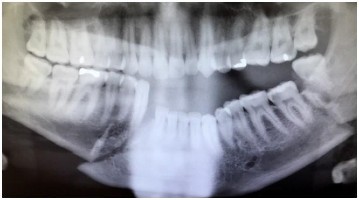

Image panoramique de la mâchoire.